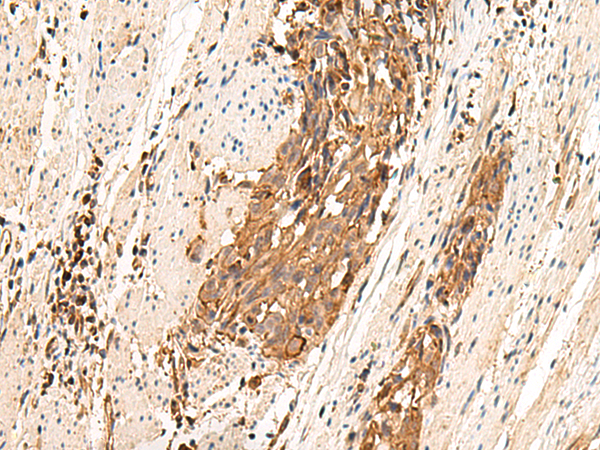

分类: 科研抗体货号: P13531别名: C3G; GRF2应用: IHC反应种属: Human